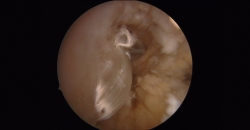

Posteriormente, desde el portal accesorio, con la ayuda de un pasahilos, se pasan los hilos del extremo distal de la plastia a través del pequeño túnel que ha dejado la aguja guía que hemos utilizado para hacer el túnel del astrágalo; de esta manera introducimos la plastia en el túnel del astrágalo y le podemos dar la tensión adecuada en el momento de colocar el tornillo (Figura 7).

El segundo tornillo interferencial de 5 × 15 mm se coloca desde el portal accesorio, con el tobillo en valgo y en neutro de flexoextensión, mientras traccionamos de la sutura para dar la tensión adecuada a la plastia.

Figura 7. Tensado de la plastia con la ayuda de la sutura de la plastia a través del túnel del astrágalo para la colocación del tornillo.